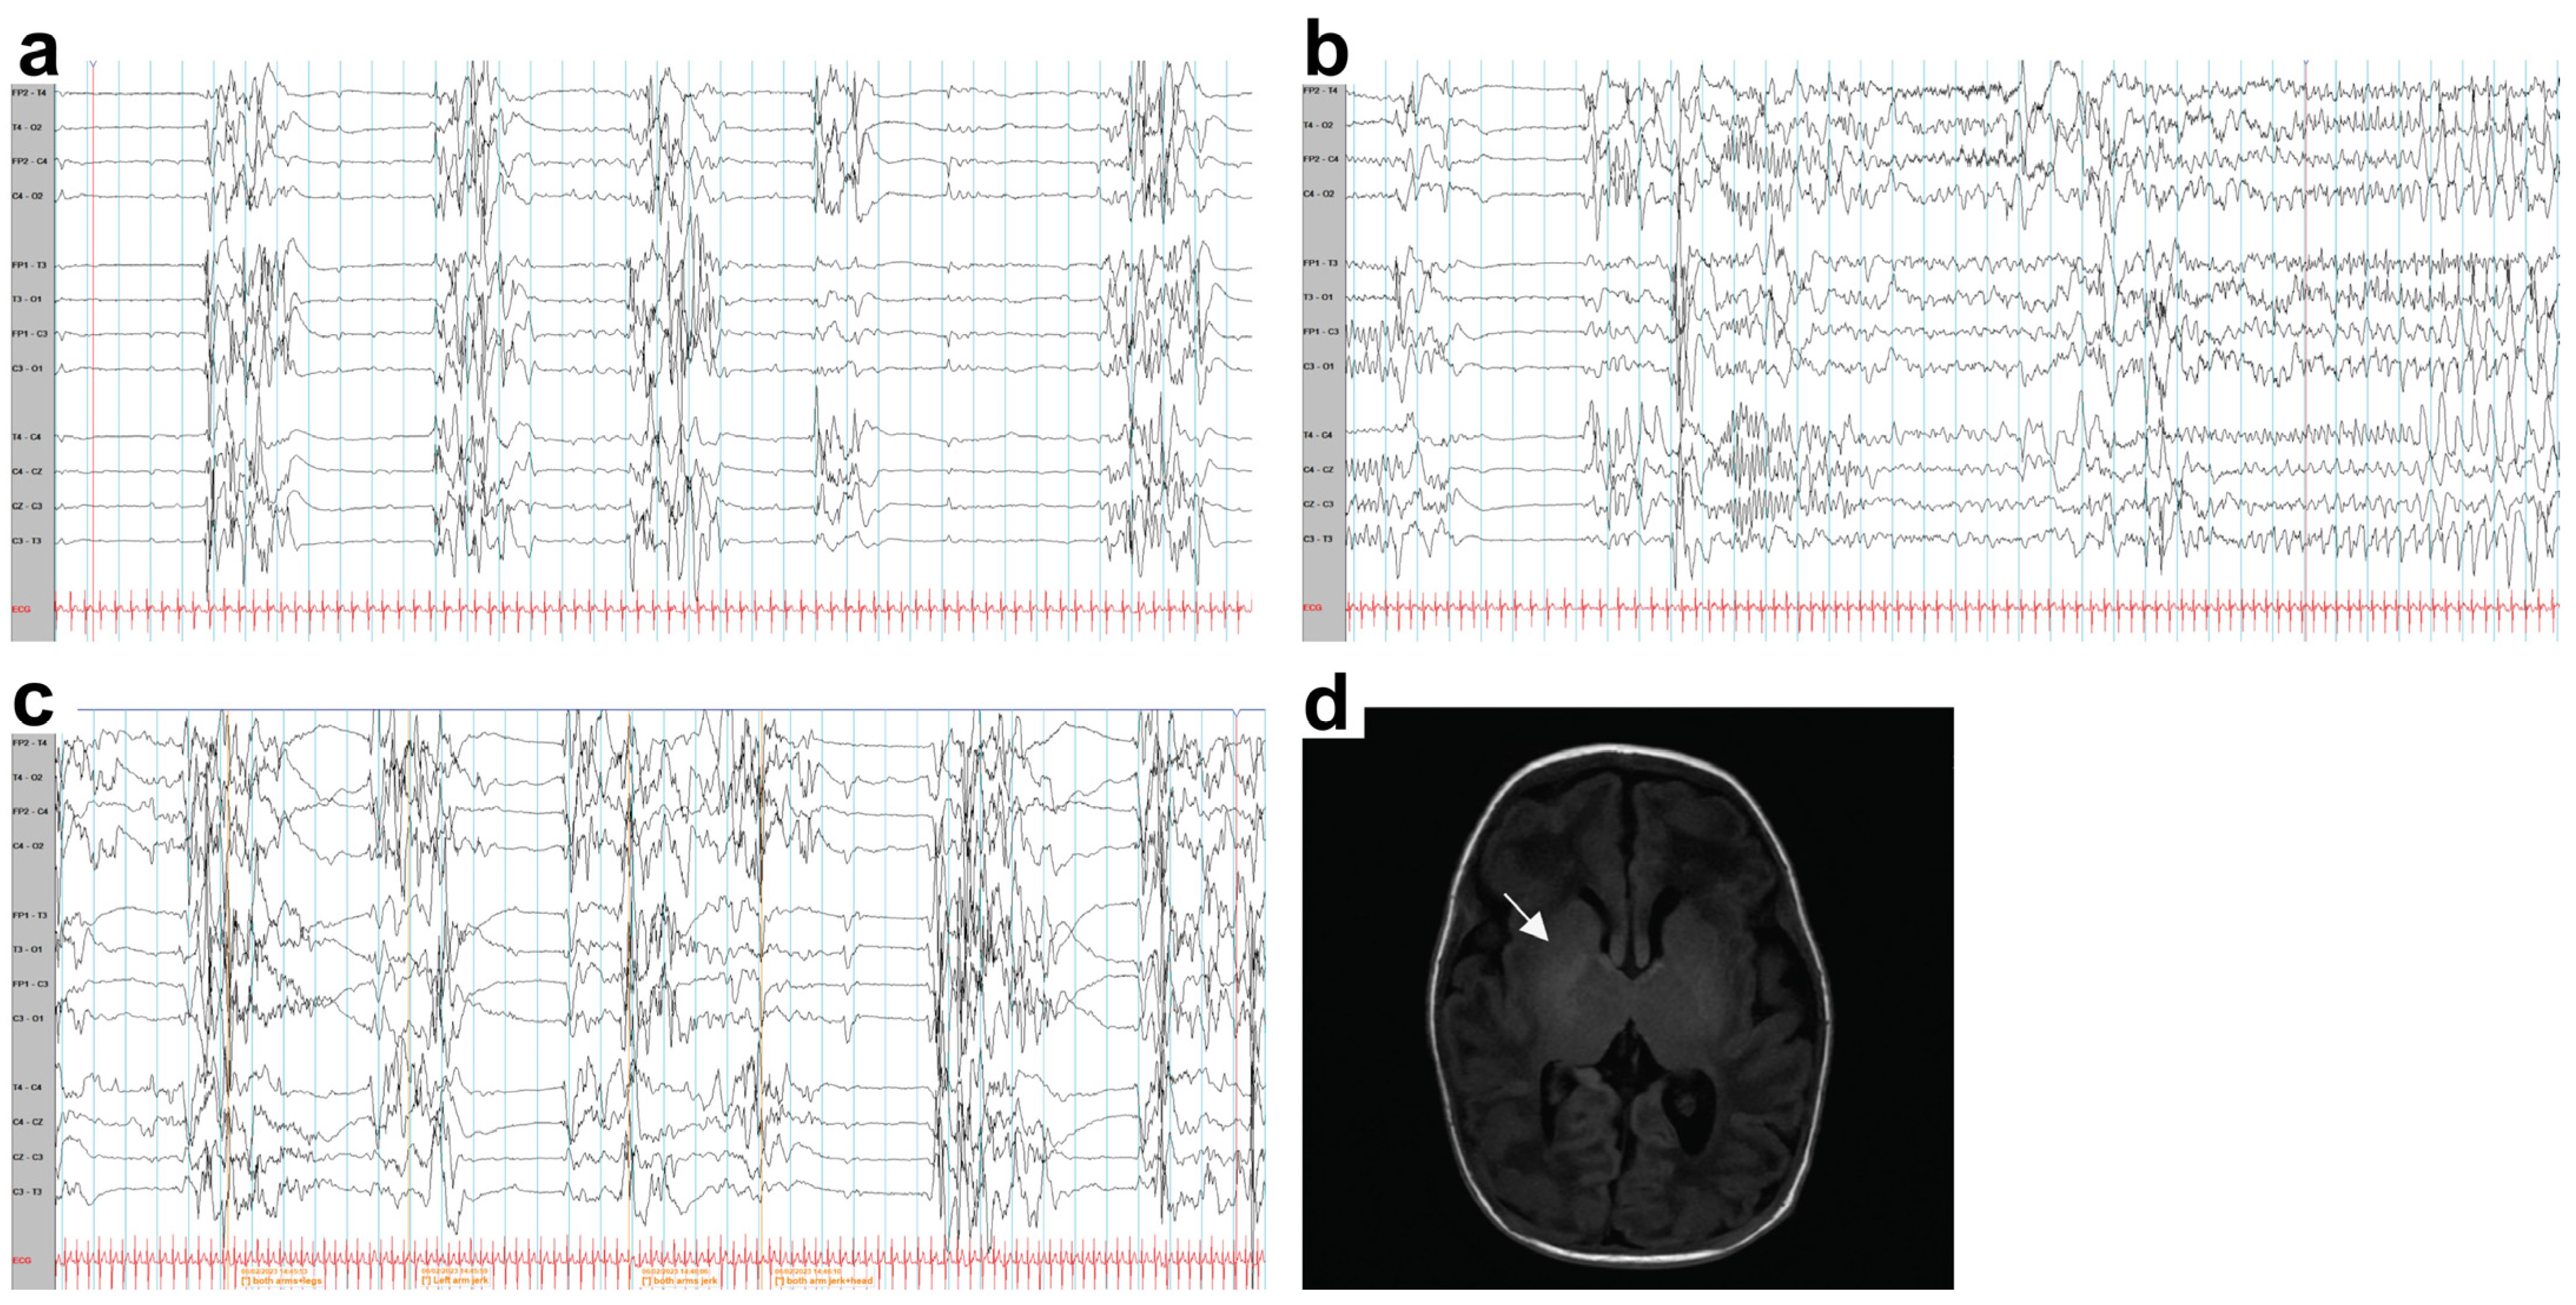

2.1. Case Report